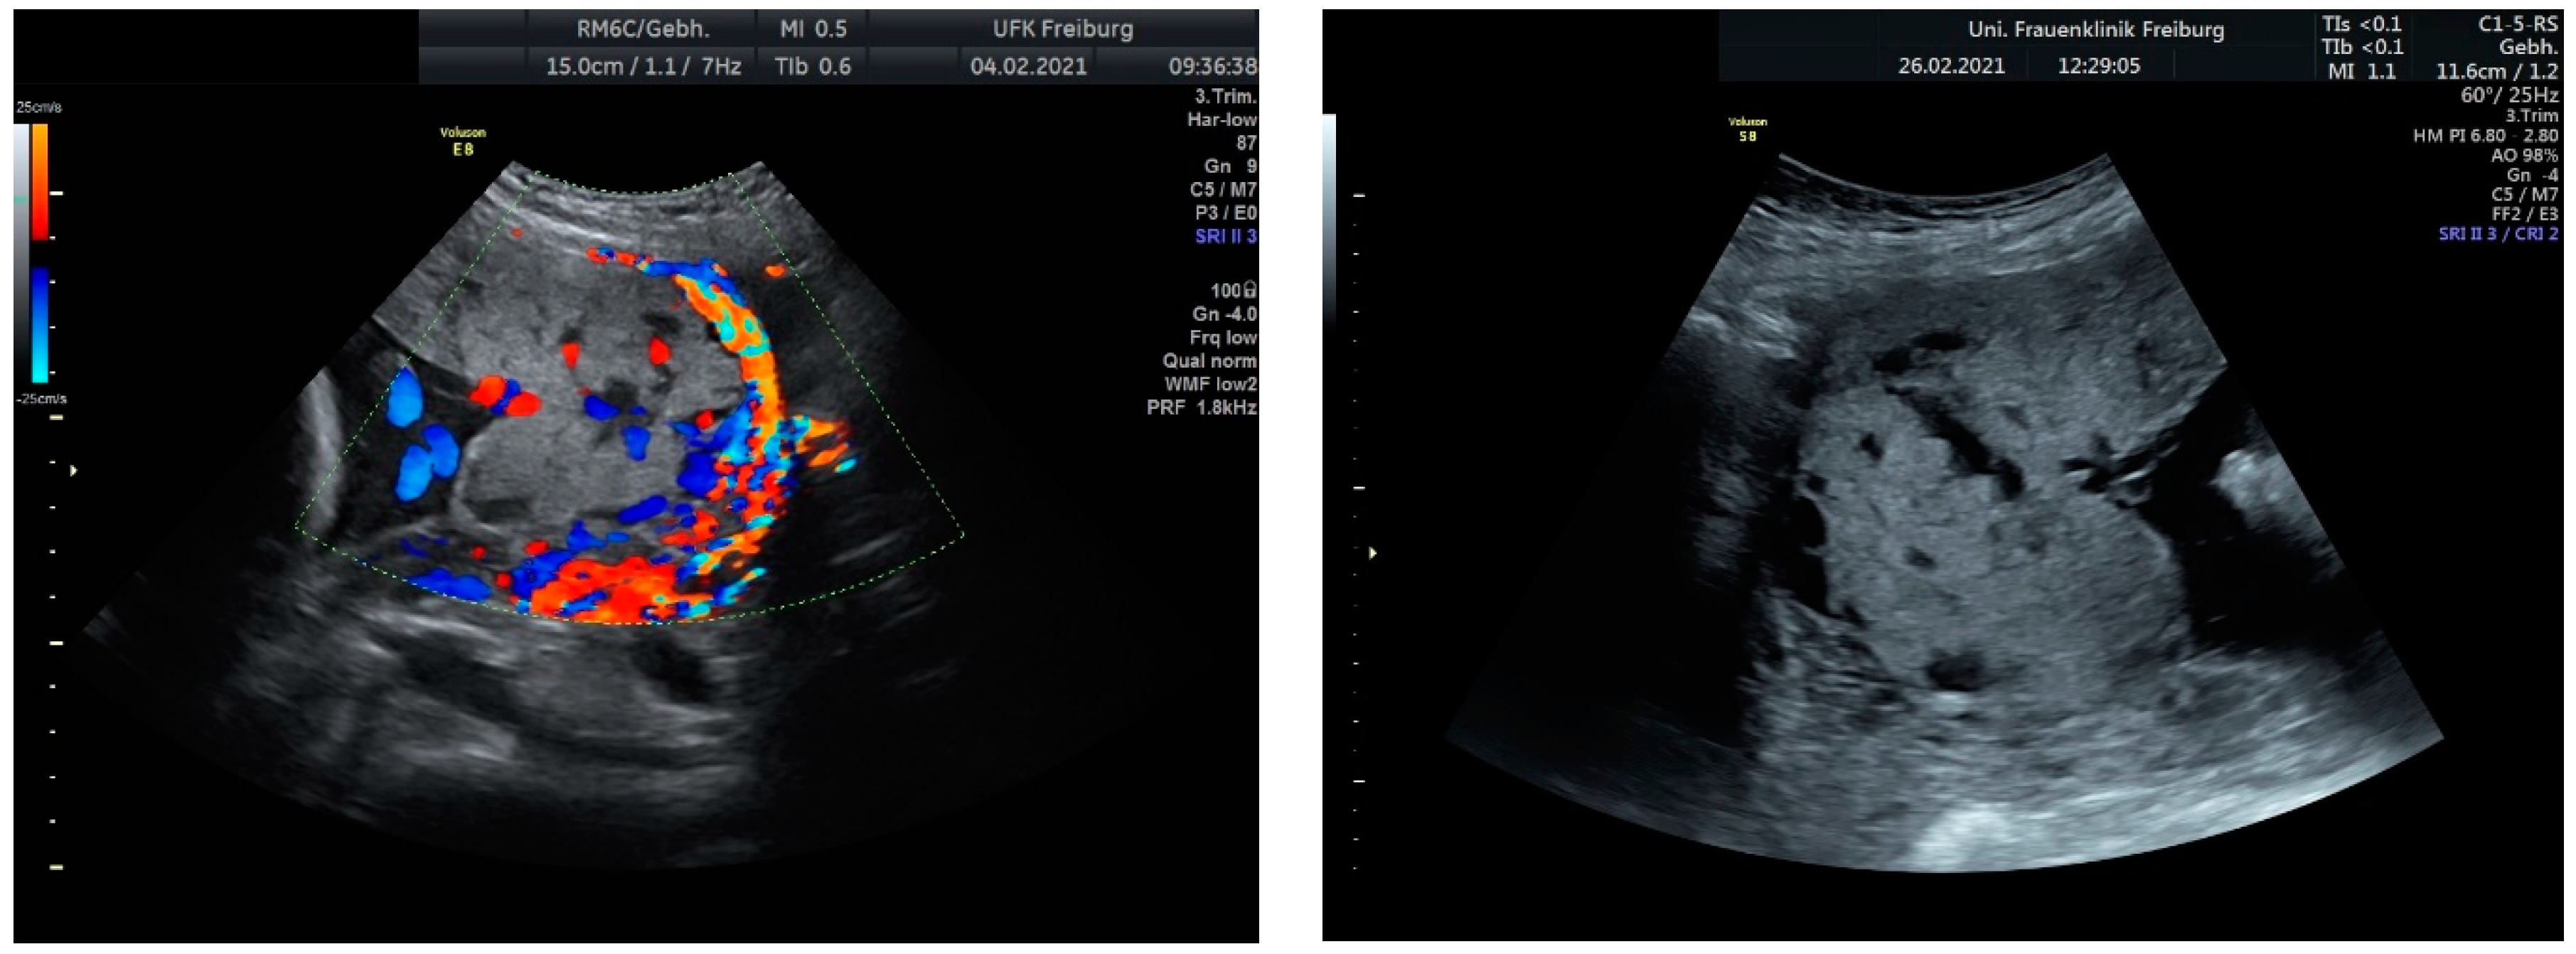

Sonographic findings (Figure 13):

Figure 13.

According to the standardized description of the European Working Group on Abnormally Invasive Placenta for ultrasound anomalies, the following anomalies may be seen: Loss of the “clear zone”—partially more in the middle (N/3):

- Abnormal placental lacunae;

- No interruption of the echoic bladder wall Myometrial thinning;

- No protrusion of the placenta into the bladder wall;

- No uterovesical hypervascularization;

- Subplacental hypervascularization.